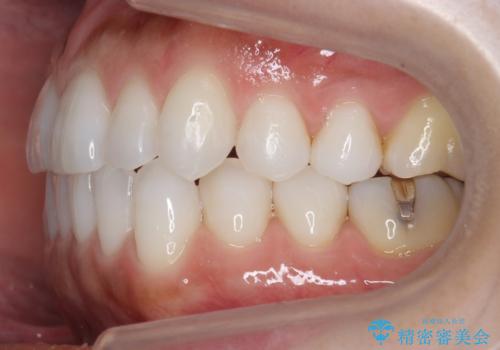

30代女性 前歯のがたつき

- 30代女性

- 矯正装置

- インビザライン

- 治療期間

- 1年5ヶ月

- 前歯のがたつきを主訴に来院。

右下の奥の銀歯も治療しています。

下の前歯を下げるため、IPR(歯をわずかに削る処置)を行っています。